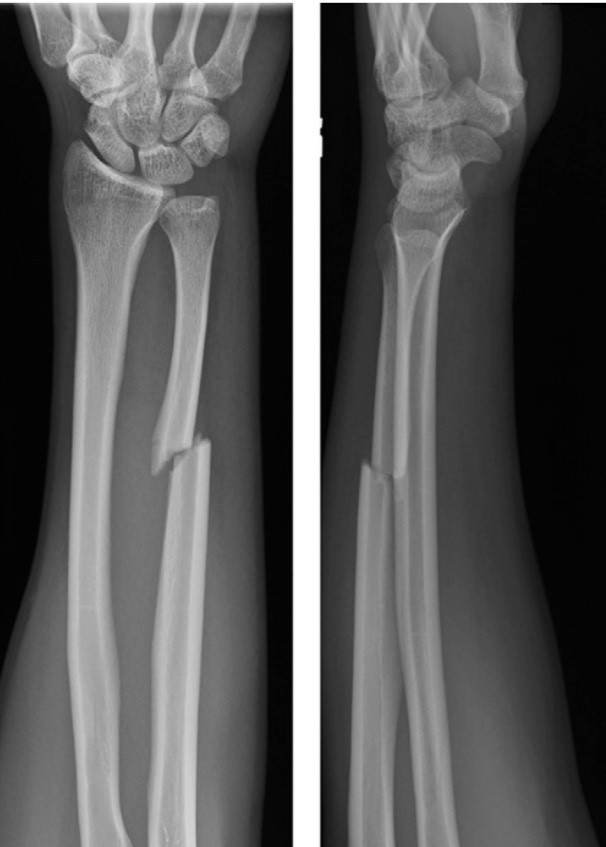

Fractures can range from simple cracks to severe, complicated breaks that affect multiple bones and tissues. Complex fractures often require advanced surgical expertise and specialized care to restore proper bone alignment, mobility, and function. With modern orthopedic techniques, patients can achieve full recovery and return to daily life with confidence.